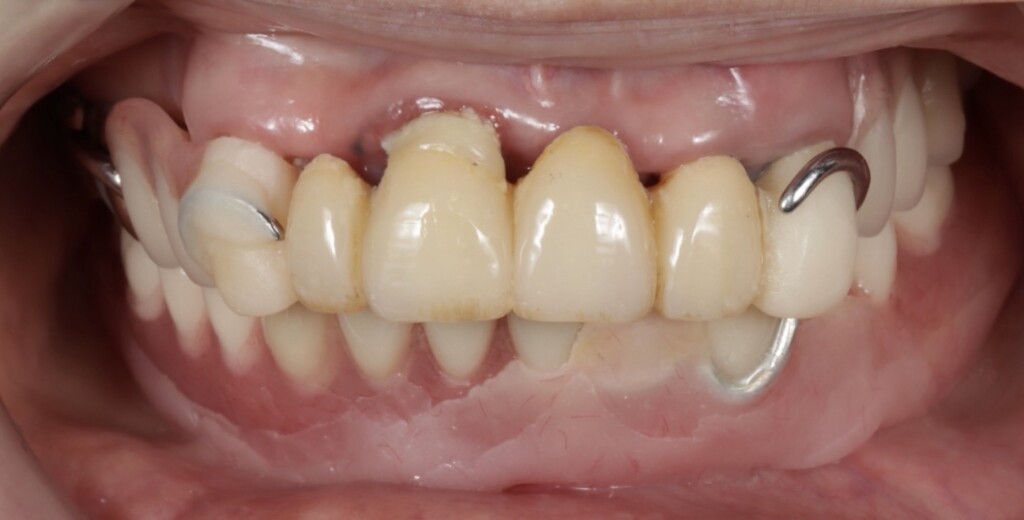

治療前の状態

口腔内の状態

写真1:口腔内の正面観

*下顎は部分入れ歯を修理した総入れ歯が装着されている

写真2:乱れた噛み合わせの平面

①下顎義歯が歯ぐきの形や機能に合っていないため動いてしまう

写真1・2の下顎の義歯は、もともと部分入れ歯として使用されていたものを、抜歯に伴い修理し、総入れ歯として使用されていました。総入れ歯と部分入れ歯は同じ「入れ歯」ですが、設計のコンセプトは大きく異なります。

今回の義歯は、もともと部分入れ歯として作製されたものを修理して使用していたため、こうした「総入れ歯としての安定に必要な設計」が十分ではありませんでした。その結果、食事のたびに動いてしまう状態につながっていたと考えられます。

②上顎の残存歯に虫歯と歯ぐきの炎症が認められ、支える力が低下している

上顎は、前歯部にブリッジ、右上奥歯には銀の被せ物が装着されている状態でした。しかし、それらを支えているご自身の歯との境目から虫歯が進行しており、残っている歯のほぼすべてに問題が認められました。特に右上の前歯は、歯ぐきの下にまで虫歯が進行しており、汚れが溜まりやすい状態となっていたため、歯ぐきにも強い炎症がみられました。また、その他の歯についても、虫歯ではない健全な歯質が歯ぐきの縁付近までしか残っていない状態で、歯としての支える力が大きく低下していました。

③上下の入れ歯の噛み合わせの平面が著しく乱れていて、歯にかかる力のバランスが崩れている

①とも関連しますが、上下の入れ歯の噛み合わせの平面が乱れていると、噛んだときに一部だけが先に強く当たり、力のかかり方が偏ってしまいます。その結果、入れ歯がテコのように動き、反対側が浮き上がるなど、不安定な状態になります。これは、テーブルの脚の高さが揃っていないとガタつくのと同じで、噛み合わせのバランスが崩れることで、入れ歯全体の安定性が大きく低下してしまうのです。